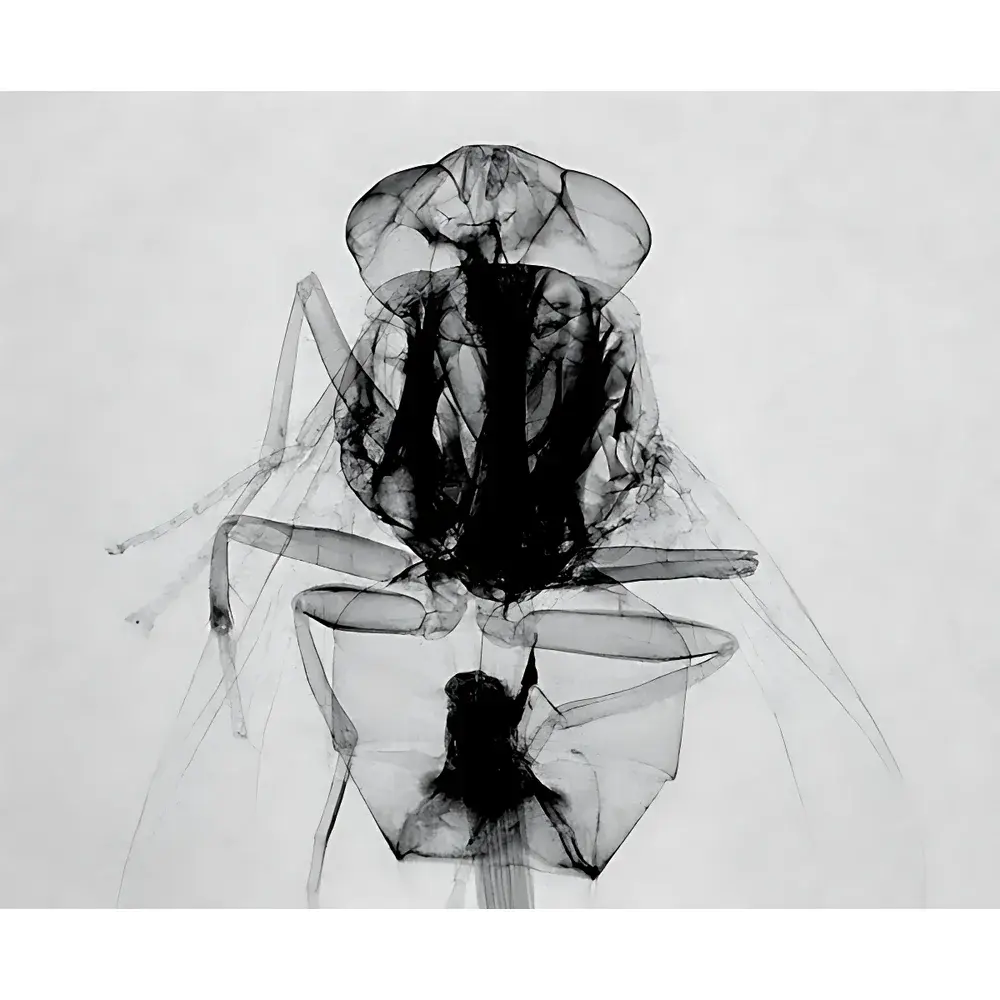

The AoLong Lab-Specific In Vivo Micro-CT Imaging System is a benchtop preclinical computed tomography platform engineered for non-invasive, high-resolution three-dimensional structural imaging of live small animals and biological specimens. Based on cone-beam X-ray microtomography (CBCT), the system delivers quantitative volumetric data without requiring tissue sectioning or contrast agent administration in many applications. It operates across a tunable tube voltage range (20–90 kV), enabling optimization for diverse sample densities—from soft tissues to mineralized structures—while maintaining sub-3-µm spatial resolution under optimal acquisition conditions. The system is purpose-built for longitudinal studies in pharmacology, oncology, orthopedics, and developmental biology, where repeated in vivo measurements must preserve animal viability and experimental integrity.

The system supports live rodent models (mice, rats), zebrafish embryos, ex vivo tissue samples, and small botanical specimens. Anesthesia-compatible animal holders with integrated temperature and respiration monitoring ports ensure compliance with institutional animal care and use committee (IACUC) standards. All hardware and firmware meet CE marking requirements for laboratory equipment (2014/30/EU EMC Directive and 2014/35/EU Low Voltage Directive). Data handling workflows support audit-trail generation and user-access logging, facilitating alignment with GLP-compliant study documentation practices. While not FDA-cleared for clinical diagnostics, the system adheres to ISO 13485–aligned quality control protocols during manufacturing and calibration.

Applications

- Developmental phenotyping in transgenic zebrafish and mouse embryos.